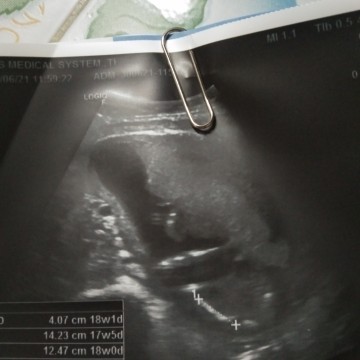

ตั้งครรภ์17วิค ไปอัลตร้าชาวด์มาอยากรู้ว่าลูกอยู่ตรงไหนค่ะ หมอไม่อธิบายให้ฟังค่ะ ขอบคุณค่ะ

น่าจะตรงที่เส้นวัดขนาดค่ะ

ตรงเครื่องหมาย + ค่ะ